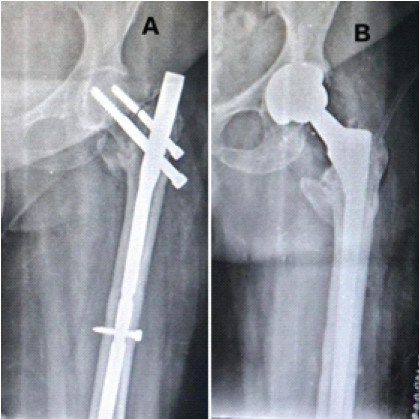

A 60-year-old male patient with TYPE 31-A2.2 pertrochanteric femur fracture of the right side (Fig. 4).

Figure 4: (a) Pre-operative anterior-posterior (A-P) view X-ray showing TYPE 31-A2.2 pertrochanteric femur fracture of the right side. (b) Post-operative A-P view X-ray showing pertrochanteric femur fracture fixed with short proximal femur nail.